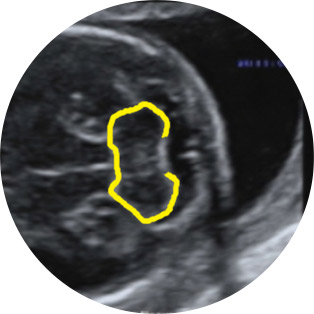

Οι βασικές τομές που λαμβάνονται είναι η διακοιλιακή και η διαπαραγκεφαλιδική τομή, όπου ελέγχεται μια πλειάδα ανατομικών τμημάτων του εγκεφάλου, όπως οι πλάγιες κοιλίες, το διαφανές διάφραγμα, οι θάλαμοι, η παραγκεφαλίδα, ο σκώληκας η 4η κοιλία του εγκεφάλου και, όταν απαιτείται, λαμβάνονται επιπλέον τομές, όπως η οβελιαία και η στεφανιαία τομή για έλεγχο των κοιλιών του εγκεφάλου και του μεσολοβίου σώματος.